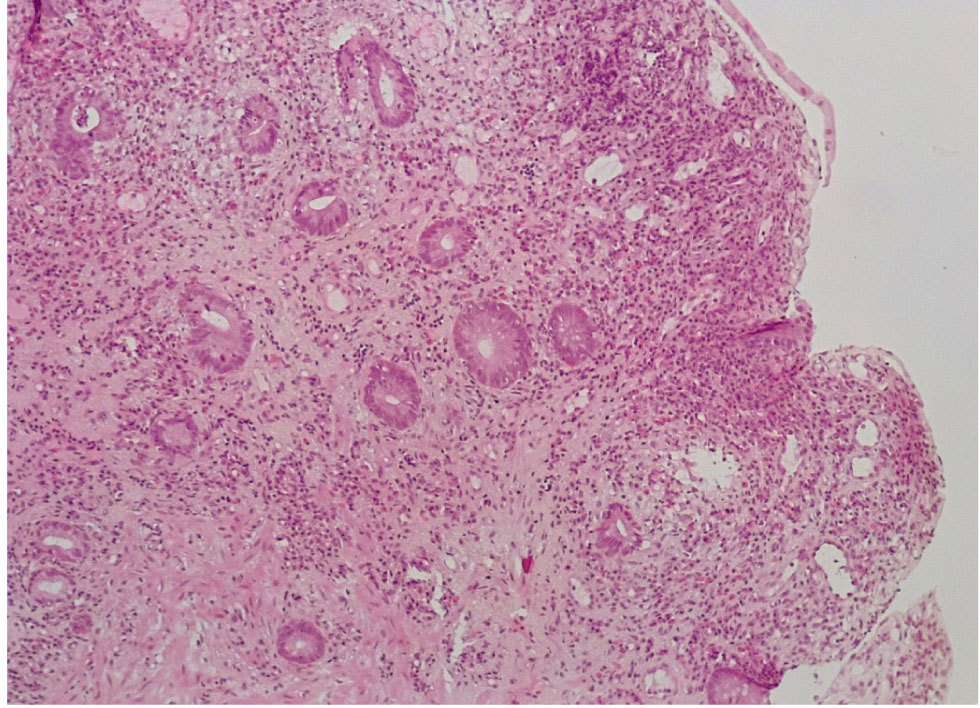

В контрольной группе биопсий слизистой оболочки (СО) толстой кишки, выполненной по поводу хронического поверхностного колита, были обнаружены следующие морфо-гистохимические изменения. СО толстой кишки была сохранена, цилиндрический (столбчатый) эпителий располагался в один слой, содержал на всем протяжении кислые гликопротеиды (ШИК-реакция). Крипты СО на всем протяжении были сформированы правильно, содержали до 12–15 бокаловидных клеток на крипту, содержали альциан+ муцин, что свидетельствовало о наличии в них нейтральных мукополисахаридов (рис. 1, 2).

Рис. 1. Контрольная группа: нормальное строение слизистой оболочки толстой кишки с сохранением цилиндрического эпителия и крипт, содержащих бокаловидные клетки. Окр. гематоксилин-эозином, ×100

Рис. 2. Контрольная группа: на поверхности слизистой оболочки толстой кишки цилиндрический эпителий сохранен, содержит кислые гликопротеиды. Бокаловидные клетки представлены во всех криптах, содержат альциан + мукополисахариды. ШИК-реакция с докраской альциановым синим, ×100